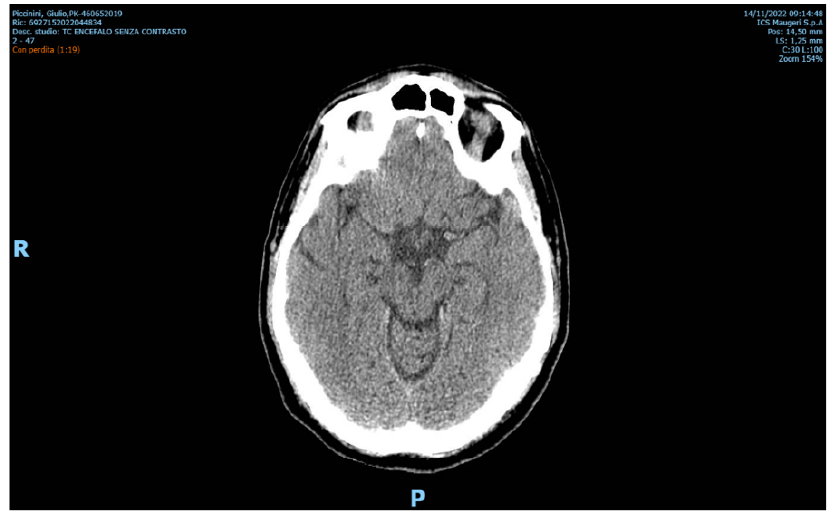

Blindness Linked to Acute Disseminate Encephalomyelitis (ADEM) and Covid 19

G Fizzotti, F Grossi, S Rivoire and P Gabanelli. 6(3): 37-40.